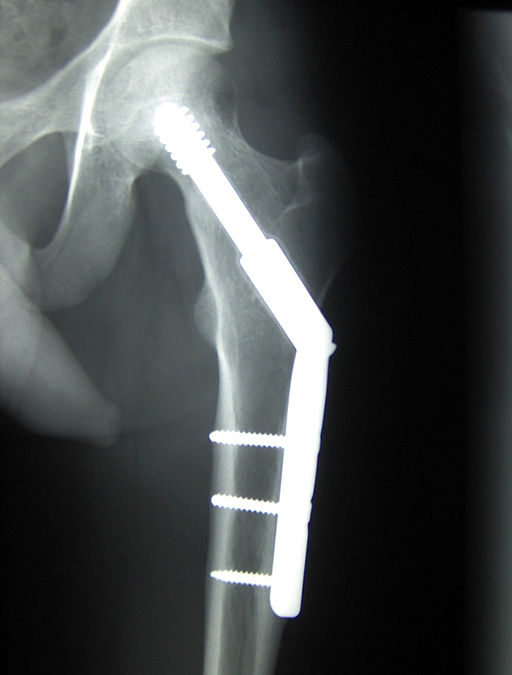

These fatigue induced fractures are frequently termed “stress fractures.” There is swelling of the bone’s surface and marrow, and subtle and tiny linear fractures; findings that normal X-rays studies are too insensitive to detect. The expense and radiation associated with MRI and CT imaging to screen for fractures are too great. More importantly, the patient’s complaints of increasing aches and pains in these bones that would prompt such studies are masked by other problems of aging, attributed to “arthritis” or getting old rather than formation of stress fractures. Measurement of collagen crosslinking, by those advanced glycation end products, is a future consideration.